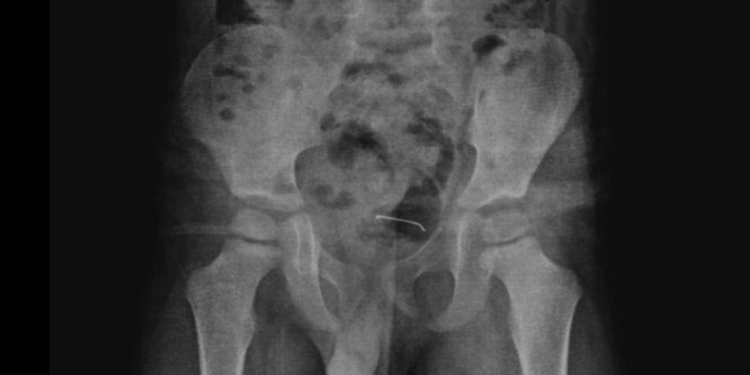

Güroymak’ta sürekli karın ağrısı şikayeti çeken 5 yaşındaki çocuk, ailesi tarafından çeşitli sağlık kuruluşlarına götürüldü. Sonuç alamayan aile, en son Tatvan Devlet Hastanesi’ne başvurdu. Burada çekilen röntgende, çocuğun mesane duvarında metal bir cisim olduğu belirlendi. 9 ay önce yutulan ve vücutta kalan 3 santimetrelik toplu iğnenin mesane duvarına yapıştığı tespit edilince ameliyata karar verildi.

Tatvan Devlet Hastanesi Çocuk Cerrahi Uzmanı Op. Dr. Tahsin Onat Kamçı tarafından gerçekleştirilen operasyonla, toplu iğne başarılı bir şekilde çıkarıldı. Gözlem altında tutulan çocuk, birkaç gün sonra taburcu edildi. Op. Dr. Tahsin Onat Kamçı “Cerrahi operasyonla 3 santimetre civarındaki toplu iğneyi çıkardık. Hastayı birkaç gün takipte tuttuk. Genel sağlık durumu iyi olan hastamızı taburcu ettik. Kesici ve delici cisimler çok tehlikeli. Bu gibi cisimlerin çocukların ulaşabileceği yerlere bırakılmaması gerekiyor” dedi.